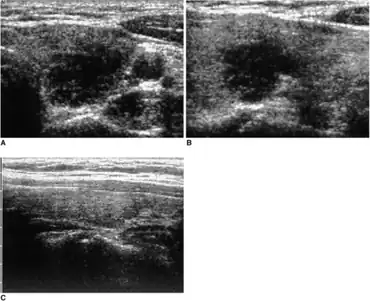

a) Transverse b) and longitudinal (B) sonograms of the left thyroid show lesion mimicking a malignant nodule (subacute granulomatous thyroiditis was confirmed via fine needle aspiration) c) one month of medication later the lesion was not clearly visable